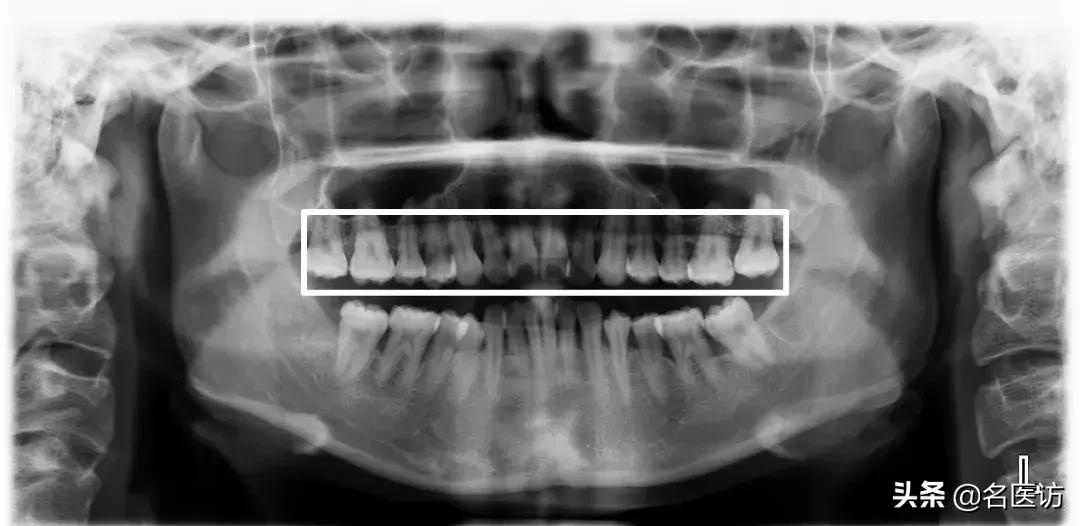

4、上颌窦

上颌窦底与上颌后牙牙根的位置关系也是矫正时要重点关注的,一般来说上颌第一磨牙与上颌窦底距离最近,但两者依然保持着“睦邻友好”的关系,如果上颌牙的某些牙根进入了上颌窦内,那么这些牙齿在矫正时移动的阻力可能会比其他牙齿大很多,可能存在这些牙齿的矫正效果不如预期的情况。另外,即使这些牙齿可以移动,但也会增加牙根吸收、牙齿移动不了的风险。

牙根穿过上颌窦